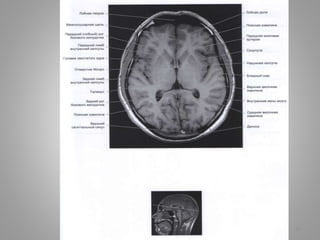

Великі цистерни головного мозку

• Велика (мозочково-мозкова) цистерна (cisterna magna, c. cerebellomedullaris) –

• Цистерна моста (препонтинна) - розташовується наперед від моста мозку, містить

базилярну артерію. Зєднується позаду з мосто-мозочково-мозковою цистерною та

субарахноідальним простором спинного мозку, попереду – з міжніжковою

цистрною.

• Базальна цистерна (c. suprasellar) має п'ятикутну форму, включає міжніжкову

цистерну (між ніжками мозку) і цистерну перехреста (між перехрестом зорових

нервів і лобними частками).

• Чотиригорбкова цистерна (вени Галена) (c. quadrigeminalis) розташовується між

мозолистим тілом і мозочком; у її ділянці можуть розташовуватись

субарахноідальні кисти

• Обвідна (охоплююча; по Синельникову - обхідна) цистерна (c. ambient) - канал

неправильної форми, що проходить по бокам ніжок мозку і даху середнього

мозку; сполучається з мостовою і міжніжковою цистернами спереду і

чотирегорбиковою цистерною ззаду.

• Цистерна бічної ямки великого мозку (cisterna fossae lateralis cerebri) -

розташовується в латеральній борозні великого мозку.

9